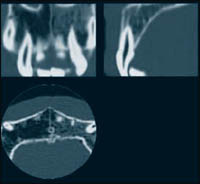

| Псевдоизображение разреза верхней челюсти, сделанное при помощи спирального компьютерного томографа |

Компания UNIDENT эксклюзивно представляет российским стоматологам высокотехнологичный трехмерный компьютерный томограф 3D Accuitomo от компании J.Morita. Технология использования конического луча компьютерного томографа позволяет получать детализированное изображение высокого разрешения исследуемой области/цилиндра диаметром 40 мм и высотой 30 мм. Трехмерный вид – осевой, коронарный и сагиттальный – позволяют осуществлять наблюдение определенной области. Возможность послойных срезов под любым углом для оптимального визуального отображения.

Разрешающая способность трехмерного компьютерного томографа 3D Accuitomo больше, чем две пары линий/мм (ЧКХ 10%). Снимки высокого разрешения имеют размер вокселя (элемента трехмерного изображения) 0,125 мм с каждой стороны. Шаг и ширина среза могут выравниваться на расстоянии от 0,125 до 2 мм.